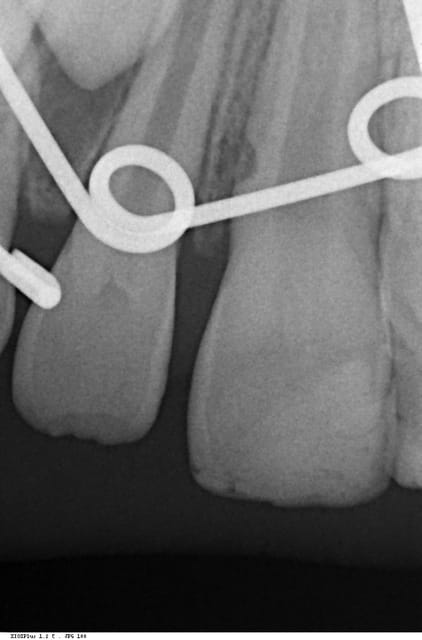

à la radio d'abord tout bon, puis un petit truc pas net sur 11 et 21 dans la partie cervicale de la racine. Aujourd'hui abcès en Mésio Vestibulaire de 11, et là, la radio ne laisse pas de doute sur la présence d'une résorption externe radiculaire cervicale. ATB pour l'abcès, mais la suite?

La 11 est toujours vitale. Je me proposais de lever un lambeau (il a 9 ans mais il est très cool), de cureter, et tenter de combler au mieux les lacunes visibles avec de la biodentine par exemple. ensuite peut-être quand même pulpectomie? La lacune visible est trop sous gingivale pour permettre un repositionnement apical du lambeau, sur une 11 à 9 ans.

Je crois me souvenir que les résorptions externes inflammatoires ont une action autolimitante sur une dent vitale, mais vue la vitesse de la perte de tissu dentaire, j'ai l'impression que si je ne fais rien la dent sera perdue. surtout que j'imagine que ce que je vois à la radio est largement sous évalué par rapport à la réalité.

en pièce jointe radio du jour de l'accident, radio intermédiaire, et radio d'aujourd'hui.

Plus j'y réfléchis, plus je trouve illusoire de penser pouvoir obturer les éventuelles lacunes visibles. Je parlais de biodentine, je me vois mal arriver à garder le site sec pendant 12 minutes, et sans que le gars ne bouge. Plutôt MTA donc. Et toujours, y a-t-il accès à ces zones? Un cône beam pourrait donner des images intéressantes.